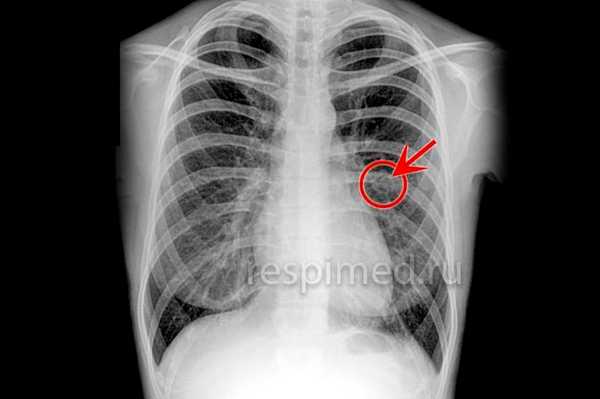

Рис. 1. Рентгенограмма грудной клетки больного с синдромом Леффлера: одиночный инфильтрат в правом легком (указан стрелкой).

Наиболее типичным рентгенол, проявлением Л. с. является тень одиночного инфильтрата, расположенного в любом отделе легкого, небольшой или средней интенсивности и, как правило, ее размеры 3—4 см в диаметре. Форма тени обычно неправильная, очертания нечеткие (рис. 1). Окружающий легочный рисунок усилен в связи с местной гиперемией. В большинстве случаев тень соответствующего корня легкого слегка расширена, структурна. При многопроекционном исследовании удается установить, что инфильтрат располагается чаще в плащевидном слое легкого. В связи с этим нередко можно выявить утолщение плевры, расположенной в непосредственной близости к инфильтрату. Характерным для динамики инфильтрата при Л. с. является его исчезновение через 1 — 3 дня после выявления; на месте бывшего инфильтрата в течение нескольких дней остается постепенно уменьшающееся усиление легочного рисунка. Такая быстрая динамика дала основание назвать эти инфильтраты летучими. Реже при Л. с. встречаются инфильтраты, принимающие форму анатомических структур — сегментов, долей, и множественные инфильтраты, к-рые иногда могут быть двусторонними (рис. 2). Быстрое исчезновение является типичным для всех видов инфильтратов при Л. с. В относительно редких случаях инфильтраты могут рецидивировать. В отдельных случаях при наличии крупных инфильтратов можно обнаружить небольшой транссудат в плевральной полости, к-рый рассасывается в течение нескольких дней.